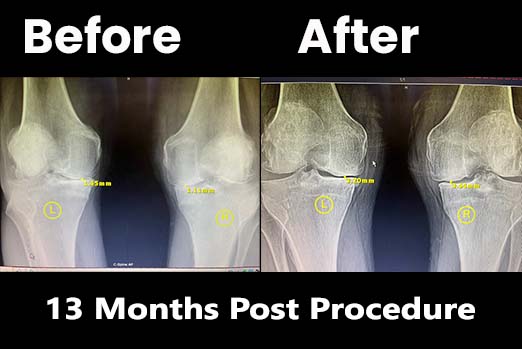

This patient had a 3.62mm improvement.

This patient had a 6.68mm improvement.

A 3.2mm miraculous joint improvement.

See this fantastic result from one of our happy patients.

Results 9 months after treatment. The patient was originally scheduled for knee replacement surgery. But 1 year after treatment the patient is now doing fantastic and pain free.